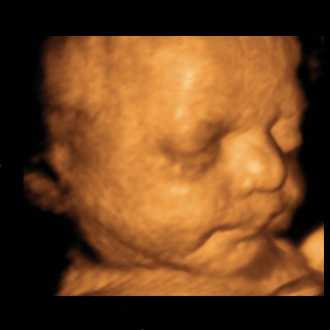

3D/4D SONOGRAPHY

3D/4D SONOGRAPHY (Live)

Built on a digital platform, the Voluson 730 utilizes advanced signal processing technology to ensure optimal image quality for high-resolution 2D, volumetric 3D and real-time 4D imaging. Image quality is further enhanced with Harmonic imaging, spectral, color and Doppler imaging,as well as our latest advance – Compound Resolution Imaging.

• High-resolution 2D, volumetric 3D and real-time 4D imaging